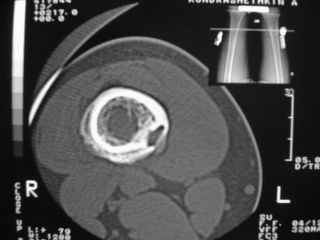

Здравствуйте, уважаемые коллеги!Представляю вашему вниманию интересный случай и пока что непонятный для меня в диагностическом плане. На днях в наше отделение (детской ортопедии и травматологии) поступил 13-летний мальчик по направлению из поликлиники с диагнозом: остеома нижней трети правого бедра.

Анамнез практически никакой: в следствие травмы (растяжение связок коленного сустава) от 07.11.2004 выполнены Rg-граммы в травмпункте и обнаружено опухолевидное образование. Первичные Rg-граммы я не публикую, так как они заметно худшего качества, да и динамики за прошедшие три недели не отражают. Болевой синдром купирован в течение трёх дней. В настоящий момент мальчика ничего не беспокоит. Ходьба не нарушена, опухоль пальпируется с трудом по задней поверхности в н\3 правого бедра, пальпация безболезненна, объем движений в суставах правой нижней конечности полный и симметричный. Кожа над опухолью не изменена.В нашей клинике проведено дополнительное обследование: общие анализы крови и мочи, биохимия крови без особенностей. Выполнены Rg-граммы на цифровом Siemens обычные и продольные томограммы срезами 3-5 мм, а также компьютерная томография поперечными срезами по 5 мм. Прошу обратить внимание, что на приведённых томограммах видны две полости 10х15 мм и 15х60 мм. Также имеются два опухолевидных образований наслаивающихся друг на друга: уплощённое и вытянутое 10х100 мм и элипсовидной формы 15х30 мм. Это хорошо заметно на фото a_1.jpg c_1.jpg и d_1.jpg. Плотность внутри полостей 125% от плотности костномозгового канала, плотность наружного опухолевидного образования 55% от плотности кортикального слоя. Также отмечается линия перелома по центру наружного опухолевидного образования.Исходя из полученных данных мнения в плане диагноза несколько разделились от 1)сочетания кортикальной фиброзной дисплазии и латентно протекавшего маршевого перелома н\3 правого бедра до 2)остеосаркомы. В отношении первого варианта не сходится отсутствие клиники при переломе такой крупной кости как бедро, второй вариант вообще оставлю без комментария, ибо некомпетентен. Хотелось бы услышать мнения коллег, с удовольствием ознакомлюсь с любыми предположениями и замечаниями.С уважением, Александр Е. КлоковОтделение детской ортопедии и травматологииБСМП г. Мурманска.